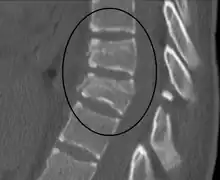

| A Chance fracture of T10 and fracture of T9 due to a seatbelt during an MVC. | |

The cause is classically a head-on motor vehicle collision in which the affected person is wearing only a lap belt.[2] Being hit in the abdomen with an object like a tree or a fall may also result in this fracture pattern.[12][10] It often involves disruption of all three columns of the vertebral body (anterior, middle, and posterior).[7][6] The most common area affected is the lower thoracic and upper lumbar spine.[6] A CT scan is recommended as part of the diagnostic work-up to detect any potential abdominal injuries.[5] The fracture is often unstable.[1]

A CT scan of the chest, abdomen, and pelvis is recommended as part of the diagnostic work-up to detect any potential abdominal injuries.[5][10] MRI may also be useful.[10] The fracture is often unstable.[1]